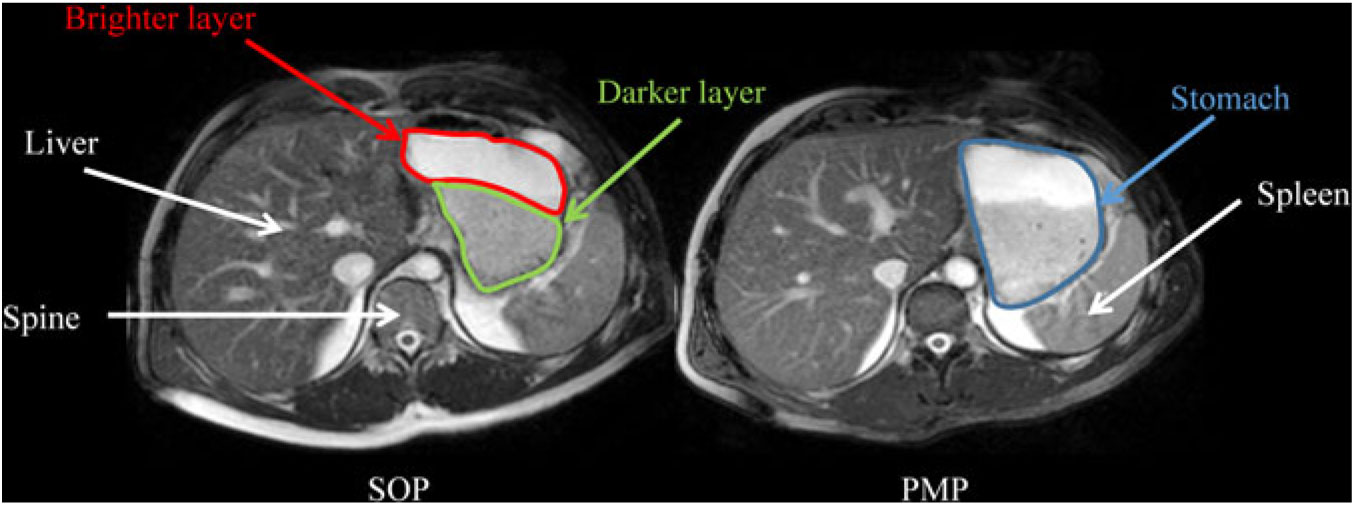

Fig. 4 shows the appearance of gastric content for SOP and PMP immediately after consumption (t = 15 min). Both porridges show clear layering (phase separation), with a brighter layer on top (consistent with a more liquid phase in this type of moderately T2-weighted images) and a darker layer at the bottom (consistent with thicker/particulate material in this type of moderately T2-weighted images). The two layers were present also at t = 45 min. However, at later time points (t = 75–135 min) the top layer was no longer visible.

Fig. 4. Representative example of axial MRI images through the same location in the abdomen of a healthy participant who consumed Scottish oats porridge (SOP) or pearl millet porridge (PMP) on two different occasions. Images were taken at t = 15 min after feeding. Anatomical landmarks such as the liver, spine and spleen are indicated by white arrows, whereas the stomach is circled in blue on the panel on the right. Both porridges showed clear layering (phase separation), with a darker layer at the bottom of the stomach (circled in yellow on the panel on the left) and a brighter layer at the top of the stomach (circled in red on the panel on the left).

The gastric appearance of both meals was similar with two separated layers being apparent immediately after feeding. The layers comprised an upper liquid phase and a lower solid/viscous phase that could be seen in the stomach. An hour later, the liquid phase was no longer visible for both meals, suggesting that gastric sieving promoted the emptying of the liquid component in the stomach contents(Reference Marciani, Cox and Pritchard51). These results with flakes are similar to those reported by Mackie et al. (Reference Mackie, Bajka and Rigby60). Half gastric emptying times were also similar for SOP and PMP. This could well relate to the isoenergetic nature of both meals, as energy content may drive gastric emptying to a greater extent compared with volume(Reference Kwiatek, Menne and Steingoetter64, Reference Calbet and MacLean65).